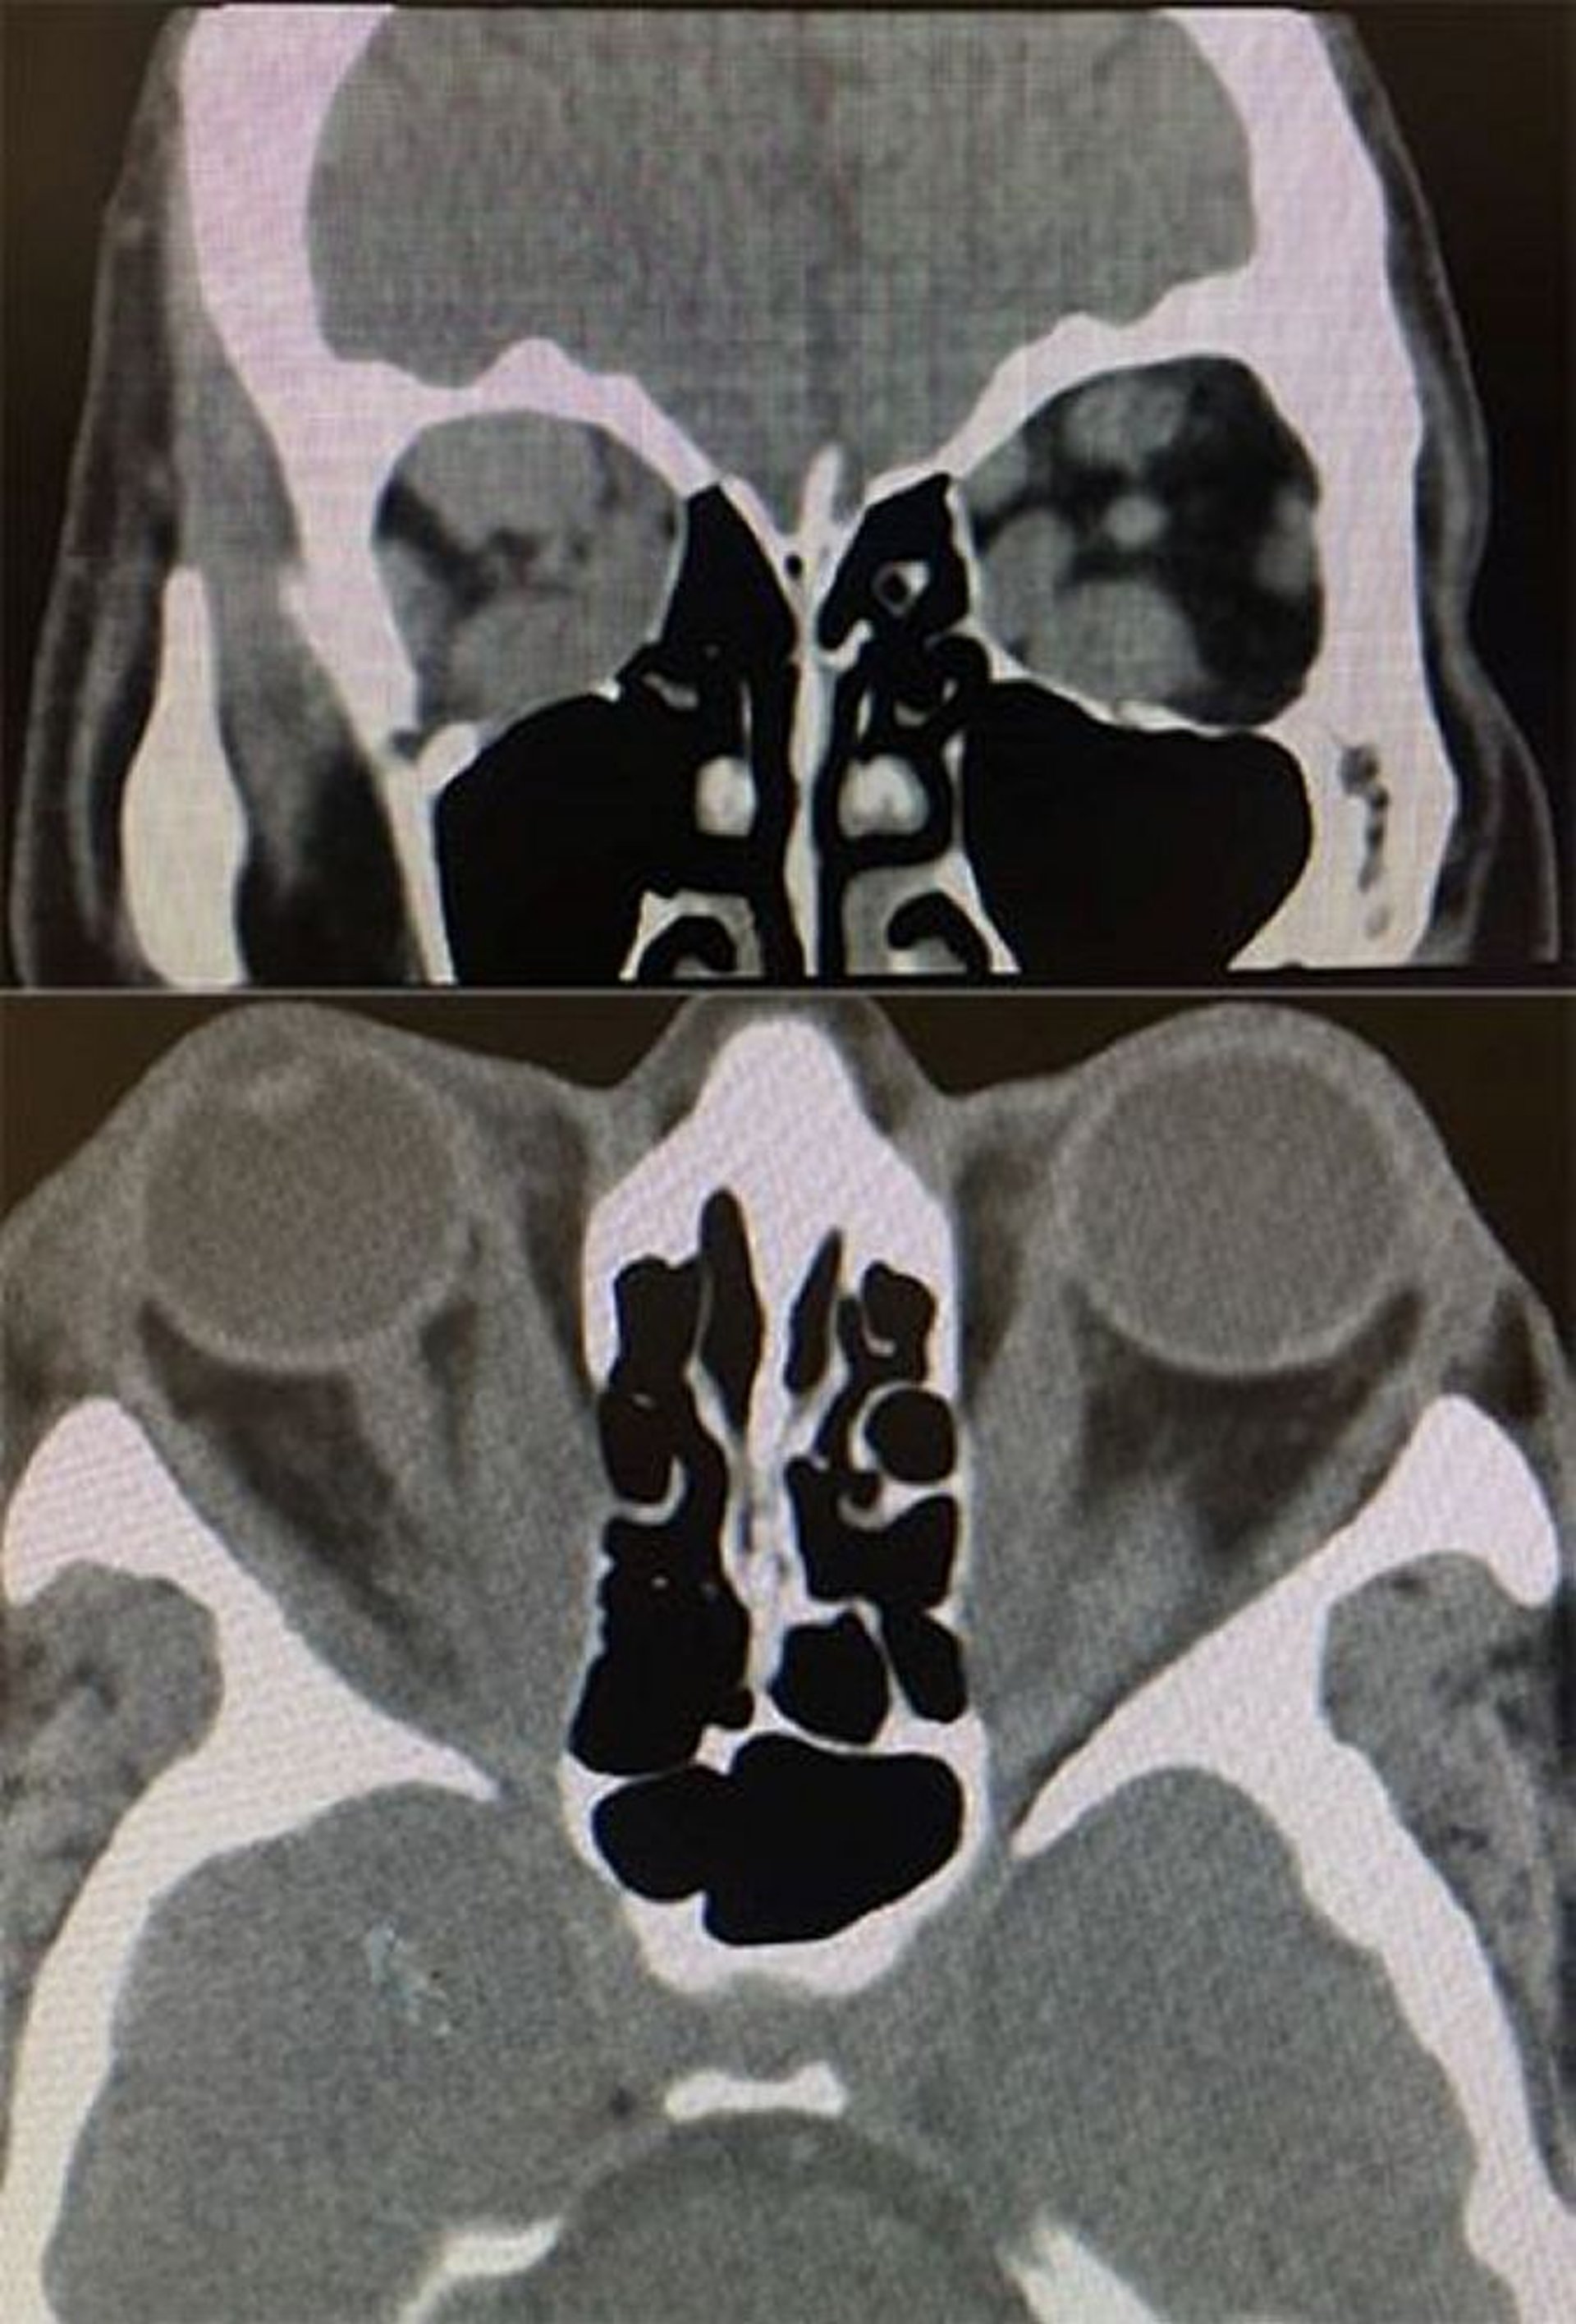

Enfermedad tiroidea ocular (TC)

En esta imagen, la TC axial y coronal muestra hallazgos de enfermedad ocular tiroidea. Inferior: la TC axial muestra un aumento del tamaño del músculo recto medial bilateral sin afectación tendinosa. Superior: la TC coronal muestra un aumento del tamaño de los músculos rectos inferior, superior y medial más a la derecha que a la izquierda.

Images courtesy of Richard C. Allen, MD, PhD.